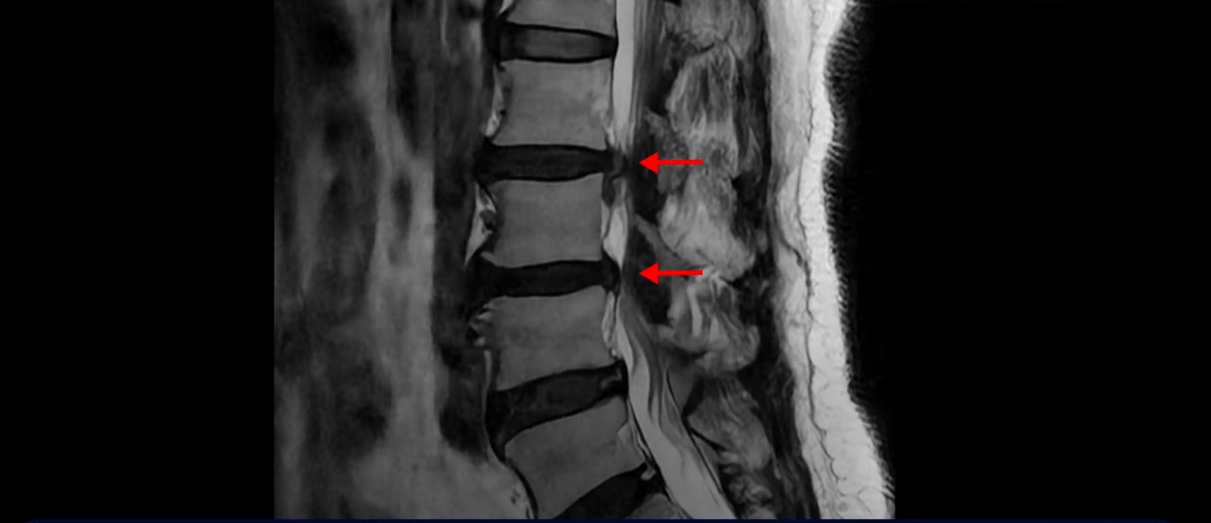

이분 MRI 보시면 2번 3번, 3번 4번이 두 마리가 특히 안 좋습니다.

2번 3번에는 우선 디스크가 파열되어 흘러내려 있습니다. 이 디스크는 파열된 지 오래된 걸로 보입니다.

이 마디는 중심성 협착도 있어서 허리 신경 공간이 많이 좁아져 있습니다.

3번 4번도 중심성 협착으로 신경 공간이 좁아져 있습니다.